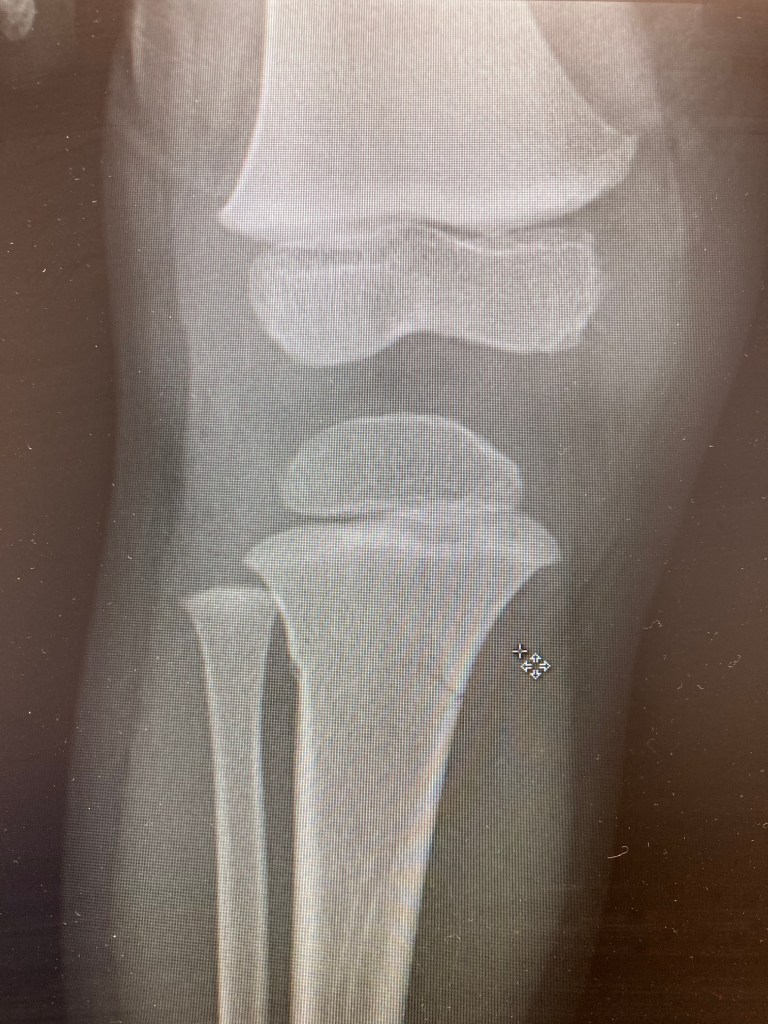

–Justus Broke his leg sledding.

My eyes followed, first and foremost, the course of his little cranium. Justus endured a fractured skull when he was 8 months old, so another could be fatal. The distance closed between him and the metal post of the fence, but his head was clear. His face did contact the chain-links, giving him a bloody lip, but nothing more. After I had raced to his side, his cries surfaced and his small voice indicated a total surprise: ”My leg hurts, dada!! My leg!!” I was shocked. No, it can’t be too serious. Didn’t he miss the pole completely? I looked down to his leg and his boot looked like it had been almost flung off his foot. Was this like that before? I took the boot off to check that everything was in tact, then touched a couple spots to see where it hurt the most. After getting a better sense for his pain level (difficult to determine with little ones), I breathed warm air on his exposed leg and carried him home.

This was a Saturday night around 6pm. We returned home and talked with Katie about the accident while taking off Justus’ snow clothes. What should we do? We were slightly skeptical that it was a broken bone, but there were a few needs to be met before making the decision to pursue urgent care. We set our wounded warrior on the couch and turned on some Charlie Brown to distract him from the pain. He was in a daze as we brought him dinner and ice packs. We asked him a few questions about the leg, but only after a little while came the true test. He had just effectively become potty trained a few months prior and he was now asking to go to the bathroom. Katie and I exchanged looks and I said the words, preparing myself to catch him. ”Okay, go ahead.” But it only took one step for him to fall to the ground in tears. I embraced him and brought him to the bathroom while Katie called the Urgent Care that was closing soon. We got ready, Justus and I (Katie needed to stay with the baby), and went to the doctor. He was such a good sport through the whole process, though we could only secure a wrap until Monday, when we would drive to a pediatric specialist for a kid’s cast. Justus chose orange. And the doctors gave us a boot to strap on for him to walk around, which he was doing within the hour, hah!

A few blessings along the way: 1. He didn’t hit his head. 2. The Urgent Care hadn’t closed yet, that Saturday night, though we almost missed them. 3. We still had our really good insurance from when Katie was a teacher. 4. Several church families came to support us with meals and company. 5. Justus was a champ and healed in 5 weeks!